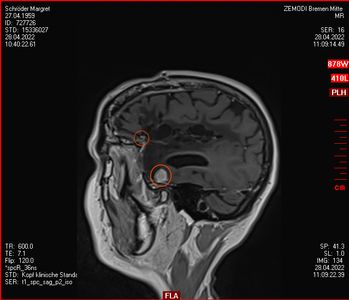

Am 03. November war mein Kontrollbesuch beim MRT. Leider ist ein kleiner Befund aufgetaucht. Schau das Video, dann kannst Du sehen.

Nun kann sich zeigen, ob die menschliche Medizin eine Lösung für mich hat. Möglichkeiten gibt es. Sogar mindestens eine, die der Neurochirurg als fein und elegant beschreibt. Gamma-Knife, eine Strahlentherapie. Klingt etwas nach Star Wars – man wird sehen,  etwas abwarten ist auch drin.

Januar 2021: Ein Kampf gegen Erbsen im Kopf mit modernen Mitteln

Also habe ich mich entschieden, dem Rezidiv nicht mehr länger beim Wachsen zuzusehen und habe Kontakt aufgenommen zur Strahlenmedizin in Hamburg, iCERA – Spezialisten für Radiochirurgie – „Präzisionsstrahlenbehandlung - geschnitten wird dabei nicht“. Das ging alles ziemlich schnell, im Dezember die Bilder auf CD nach Hamburg geschickt, ein Telefongespräch mit dem Professor, der zu einer Vorstellung bei ihm geraten hat, ein Vorgespräch im Januar und nun ist es am 26.01.2021 schon passiert – das Gammknife hat aus fast 200 Strahlenquellen für ca. 20 Minuten aus verschiedenen Richtungen auf den Tumor „geschossen“, so dass am Tumorpunkt die Strahlen zusammenfanden und so gemeinsam in diesen paar mm³ genug Energie entstand, um einen Schaden an den Zellen anzurichten ohne das gesamte Gehirn zu schädigen. Große Medizintechnik der Neuzeit. Meine Krankenkasse zahlt, was erstaunlicher Weise nicht für alle Kassen gilt.

2. November 2021: Leider etwas gewachsen

Heute war ich im MRT im Bremen. Der Befund des auswertenden Arztes ist, dass er der Meinung ist, dass der Tumor etwas gewachsen ist. Ich habe mir die Bilder angesehen und versucht diese Aussage zu verstehen. Vermutlich ist sie richtig, aber das Wachstum ist nicht heftig nur vielleicht von 0,7 cm auf 0,8 cm. Aber Gamma-Knife hat es offensichtlich nicht entfernt.

Heute war der Termin beim Chirurgen, leider schon um 9:00 Uhr und natürlich wollte ich die knapp 20 km mit dem Rad zurück legen, Stephan wollte gerne mitkommen. Leider war die bereits abgegebenen CD nicht eingelesen worden und so musste erstmal die Datenverarbeitung arbeiten und wir warten, bis wir eine Auskunft bekommen konnten. Fazit: Der bestehende Tumor ist kaum gewachsen. Aber es hat sich leider ein 2. Fund ergeben, sehr klein aber deutlich sichtbar. Aber Maßnahmen sind erstmal nicht notwendig.